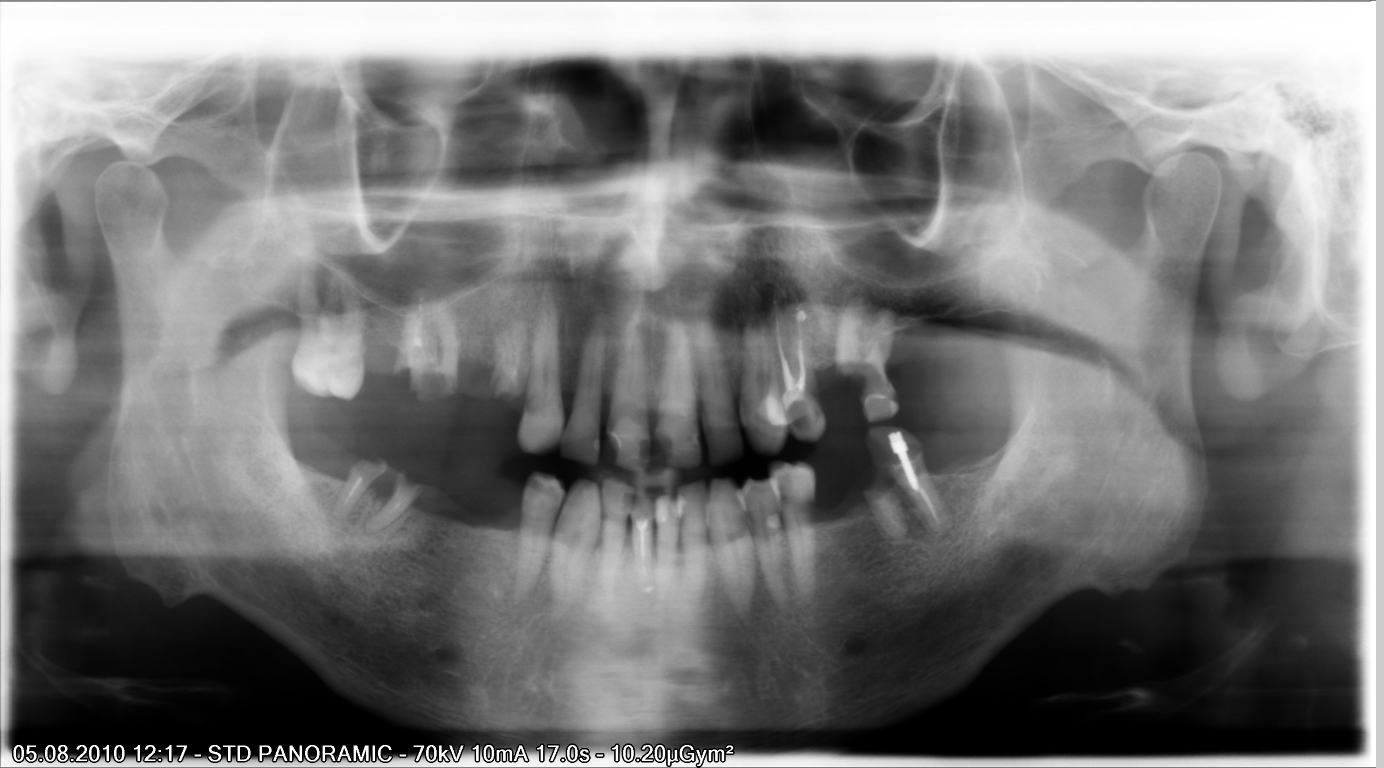

В период беременности рентген обычно не делается. И хотя при стоматологической диагностике область живота не подвергается излучению, лучше не рисковать.

Рентген зубов делают лишь, когда велика вероятность воспаления, угрожающего здоровью матери. При этом применяются радиовизиографы с минимальной дозой облучения, а также используются защитный воротник и фартук.

И все же, идеальным вариантом было бы избежать рентгеновского излучения в период вынашивания ребенка. А значит, придя на прием к стоматологу, пациентка должна проинформировать о своем положении врача.